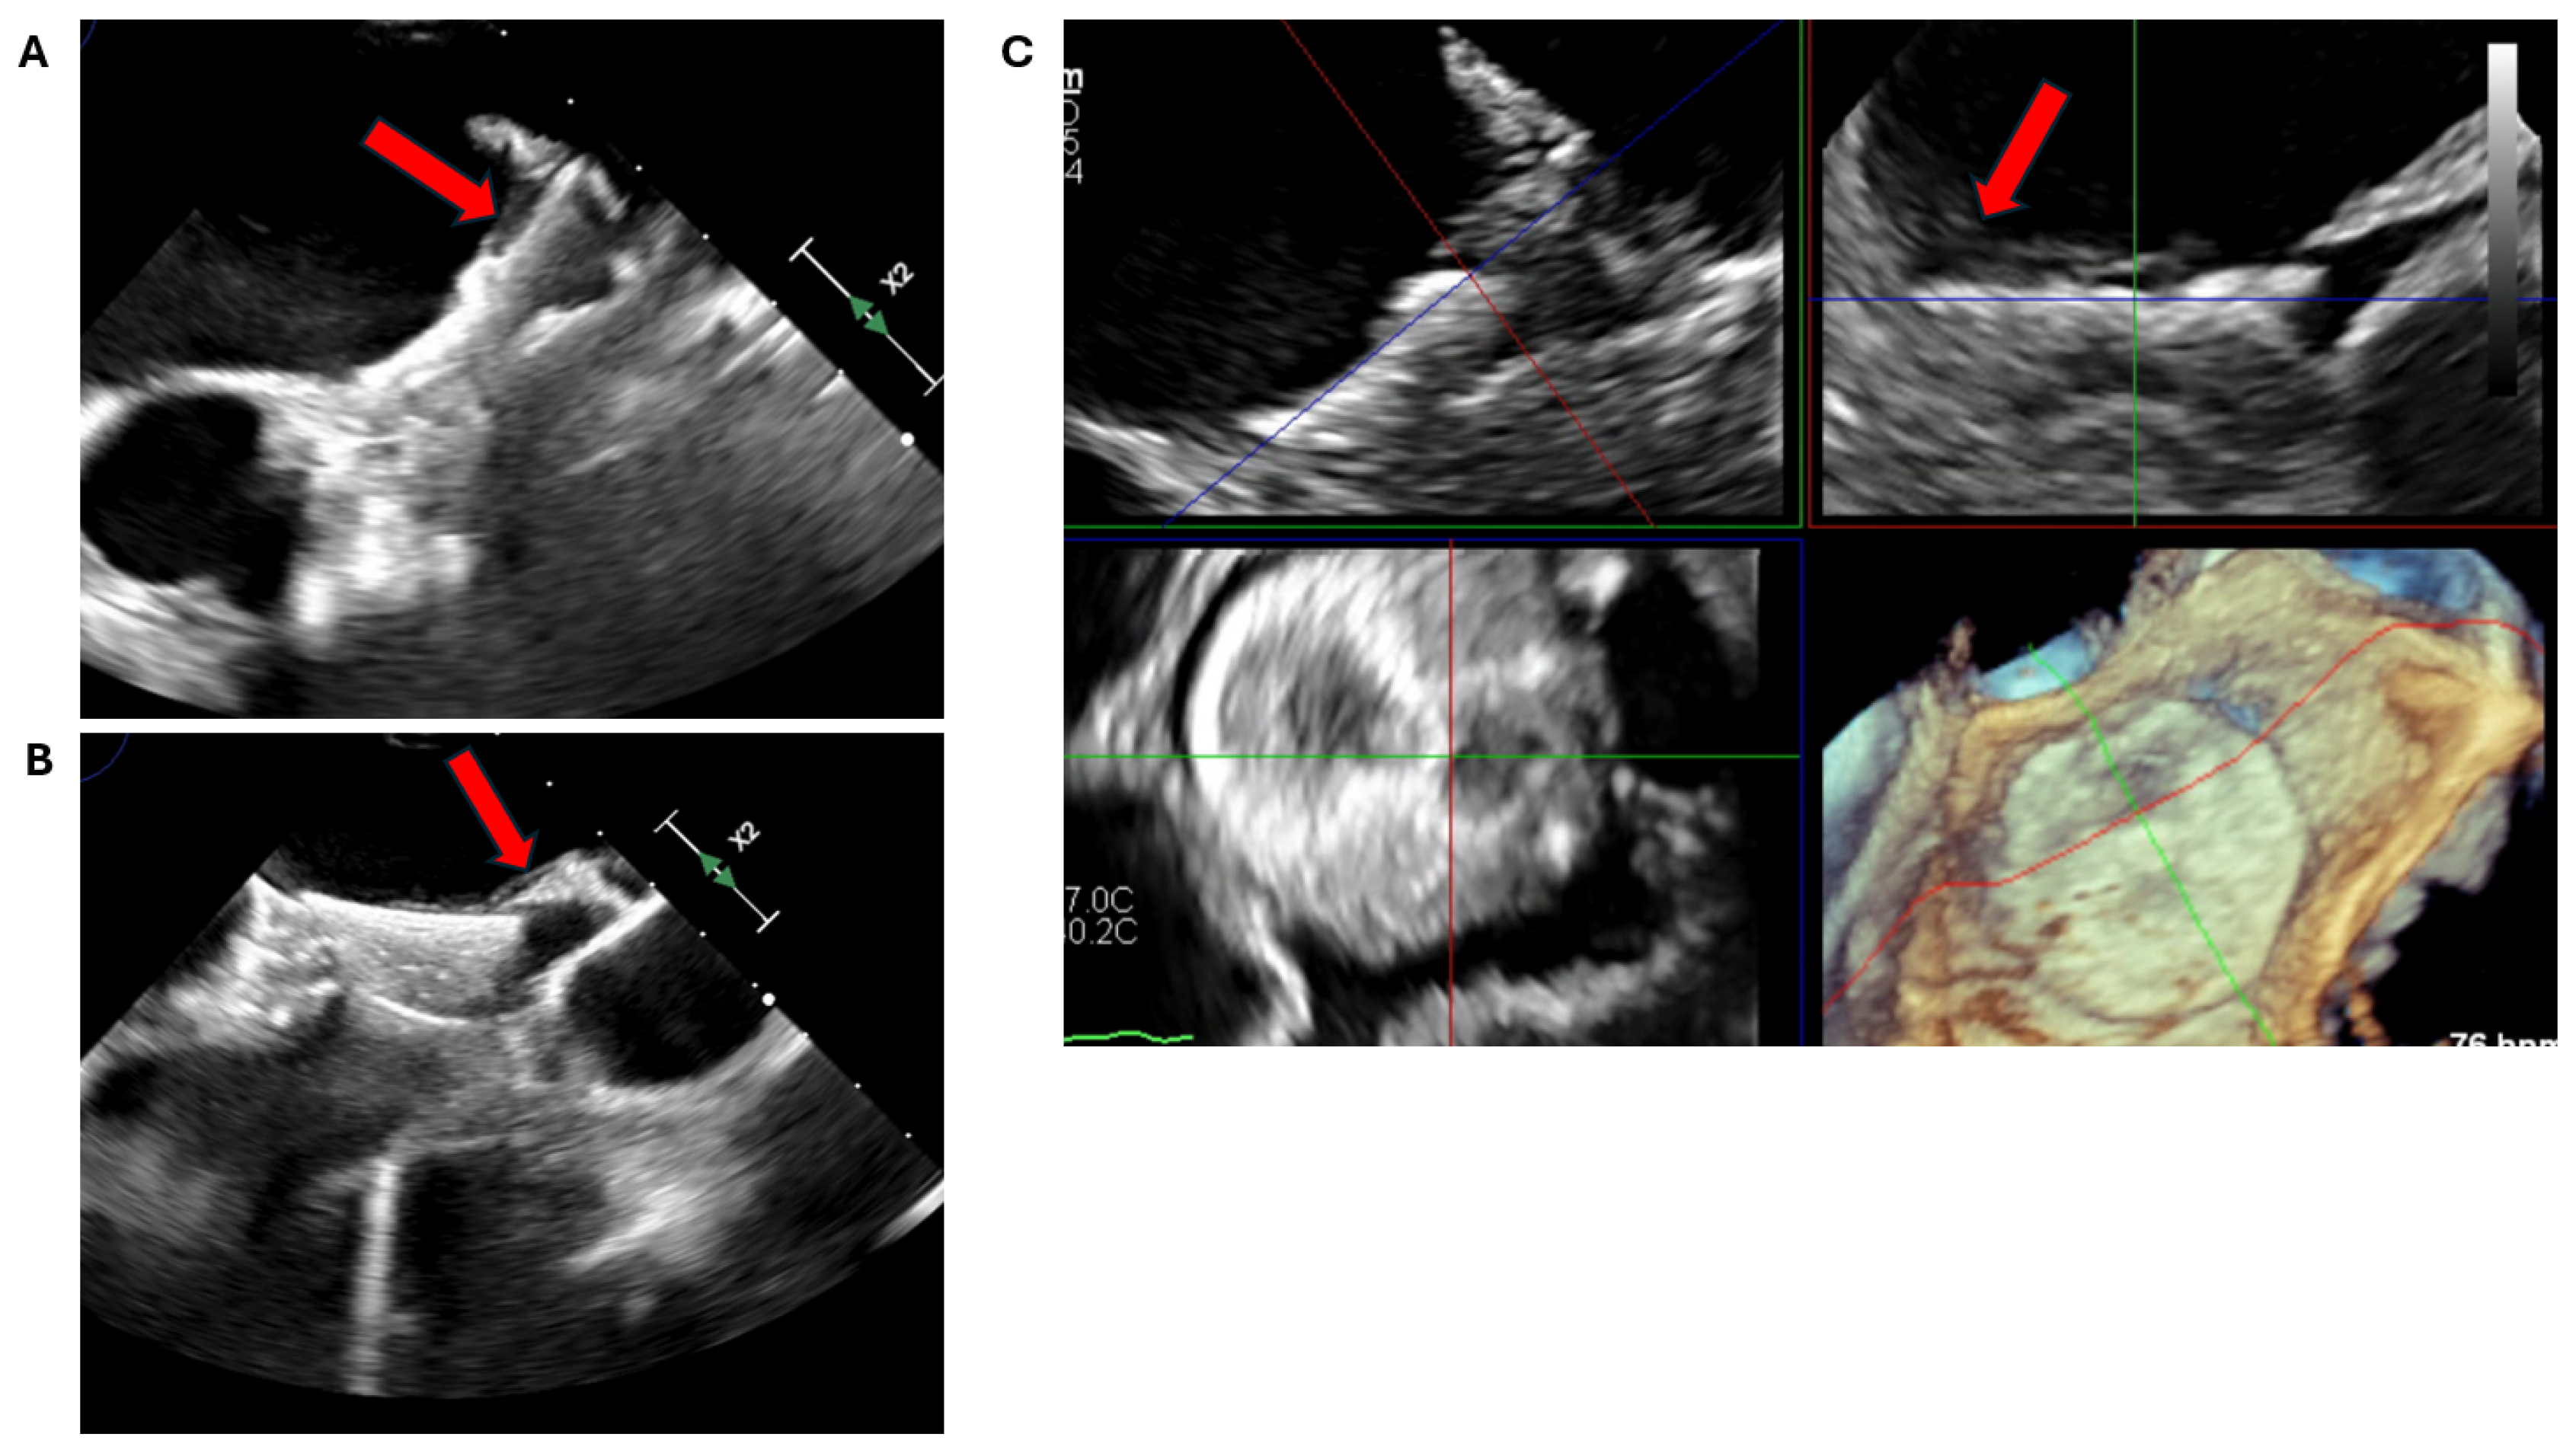

2.2. Transoesophageal Echocardiography

2.2.1. LAA Thrombus Assessment

2.2.2. LAA Measurements (Anatomy and Morphology)

2.2.3. Intra-Procedural TOE